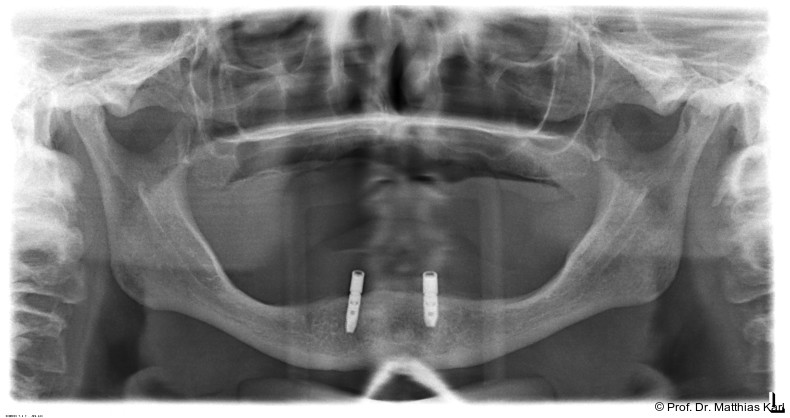

Die Insertion von zwei zahnärztlichen Implantaten zur Verankerung einer abnehmbaren Deckprothese stellt eine kosteneffektive Therapie dar, welche die Kaufunktion verbessert und zu hoher Patientenzufriedenheit führt, weshalb diese Versorgung in mehreren Ländern als „standard of care“ angesehen wird.1, 6, 14 Die dabei genutzten Verankerungselemente, welche die Prothese mit den Implantaten abnehmbar verbinden, sind entscheidend für den Prothesenhalt, die Patientenzufriedenheit und den klinischen Erfolg.14 Stege, Kugelkopf­anker und Locatoren werden hierfür häufig genutzt und führen zu einer Verbesserung der mundbezogenen Lebensqualität.4–6, 14 Die in Deutschland weitverbreiteten Doppelkronensysteme konterkarieren aufgrund der hohen Herstellungskosten die Grundidee einer kosteneffektiven Grundversorgung.8, 10, 15